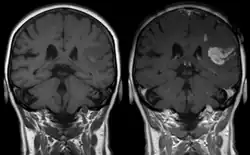

As first postulated by Harvey Cushing, raised intracranial pressure is the primary cause of the Cushing reflex.[3] Furthermore, continued moderate increases in cranial pressure allows for the Cushing reflex to occur. In contrast, rapid and dramatic pressure rises do not allow for the mechanism of the reflex to sufficiently take place.[12] Elevated intracranial pressure can result from numerous pathways of brain impairment, including: subarachnoid hemorrhages, ischemia, meningitis, trauma, including concussions, hypoxia, tumors, and stroke. In one study, it was confirmed that raised ICP due to subarachnoid hemorrhaging causes mechanical distortion of the brainstem, specifically the medulla. Due to the mechanism of the Cushing reflex, brainstem distortion is then swiftly followed by sympathetic nervous system over activity.[13] In addition, during typical neurosurgical procedures on patients, especially those involving neuroendoscopic techniques, frequent washing of the ventricles have been known to cause high intracranial pressure.[7] The Cushing reflex can also result from low CPP, specifically below 15 mmHg.[14] CPP normally falls between 70-90 mmHg in an adult human, and 60-90 mmHg in children.